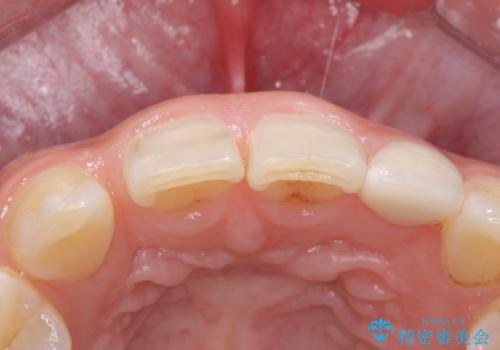

- 左上の前歯の変色が気になるとのことで来院されました。

もともと小さい歯(矮小歯)に樹脂が盛り足されている状態でした。

今後の変色をなくすために樹脂ではなくセラミックでの治療を行います。

セラミックでの治療をすることにより今後の変色を抑えることができます。

色・形ともに改善することができ大変喜んでいただけました。